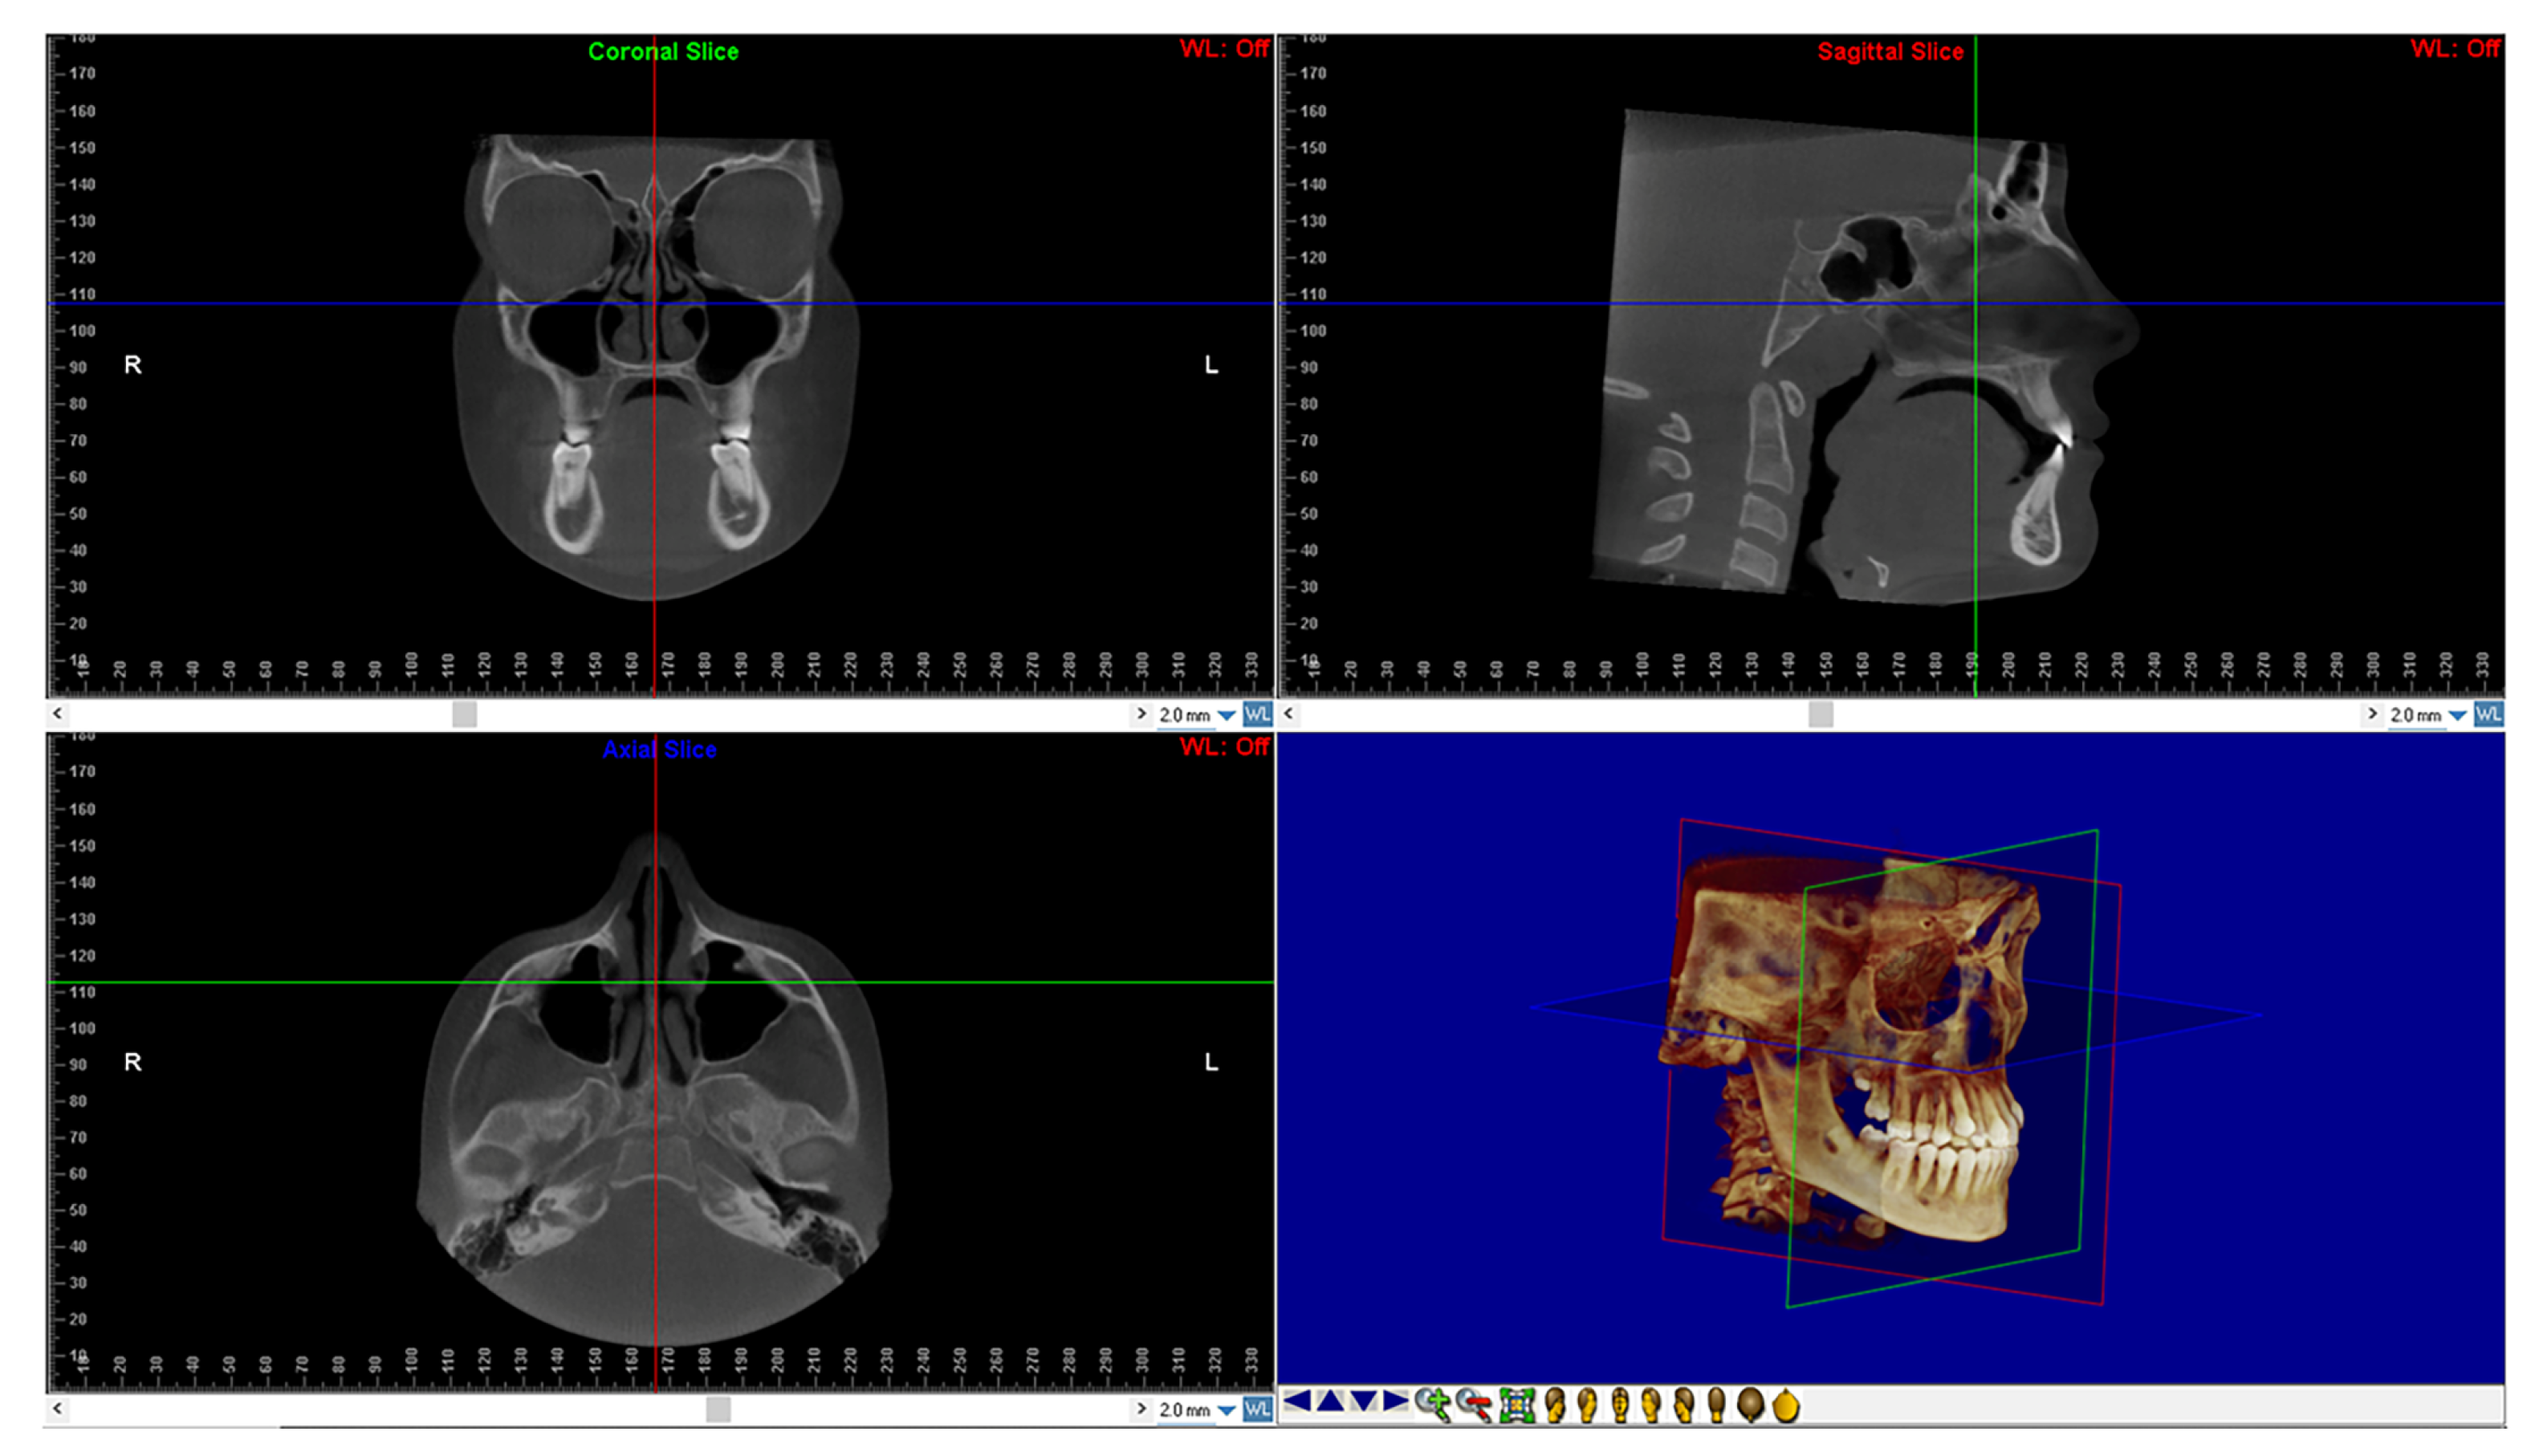

After, DICOM files of all CBCTs were imported into the Dolphin 3D software (Dolphin Imaging1, version 11.0, Chatsworth, CA, USA) to perform the reorientation of the skull according to a validated protocol [24,25] (Figure 1).

Figure 1.

Head reorientation in the axial, sagittal, and coronal planes of CBCT scans. The 3D image shows the head orientation in 3D space.